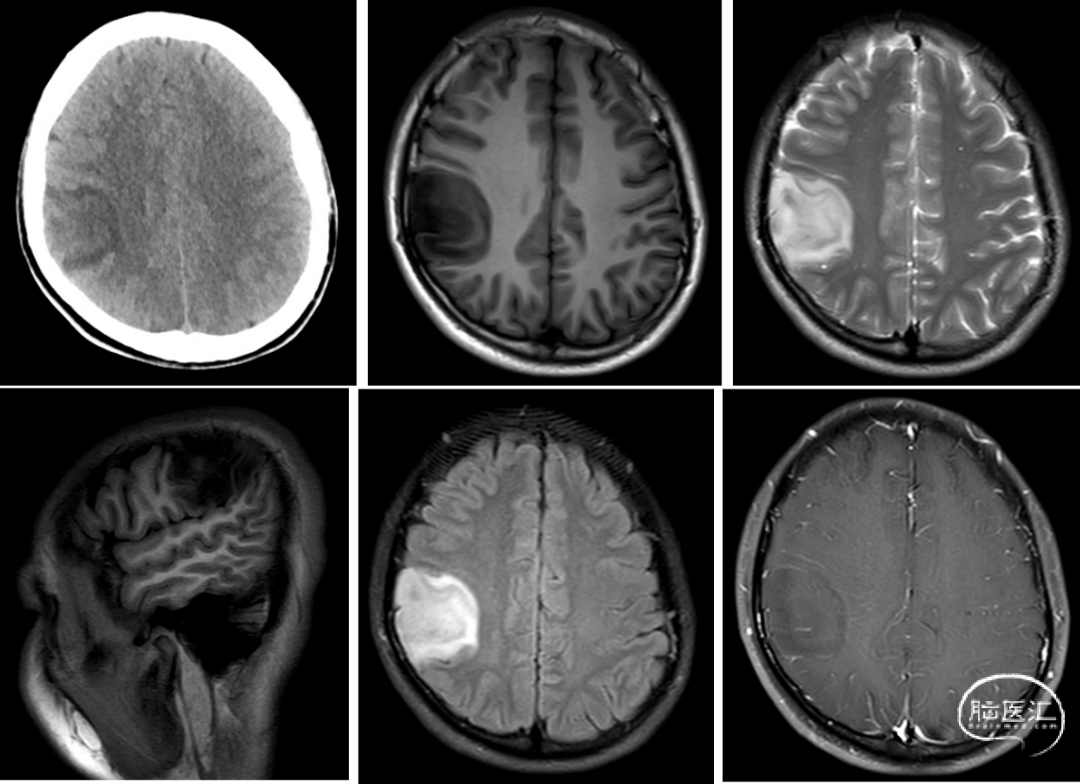

术前影像学检查:

影像学描述:头颅CT提示右侧顶叶低密度病灶;头颅MR提示右侧顶叶见一异常信号肿块,边界尚清,范围约38mm×40mm。病灶T1WI呈稍低信号,T2WI呈稍高信号,增强扫描显示肿块未见明显强化,病灶周围水肿不明显,局部脑沟稍变浅,颅内中线结构向左侧轻微移位。脑池、脑裂未见增宽。颅骨未见异常。

影像诊断:右侧顶叶异常信号肿块,考虑低级别胶质瘤(多为低级别星形细胞瘤可能)。